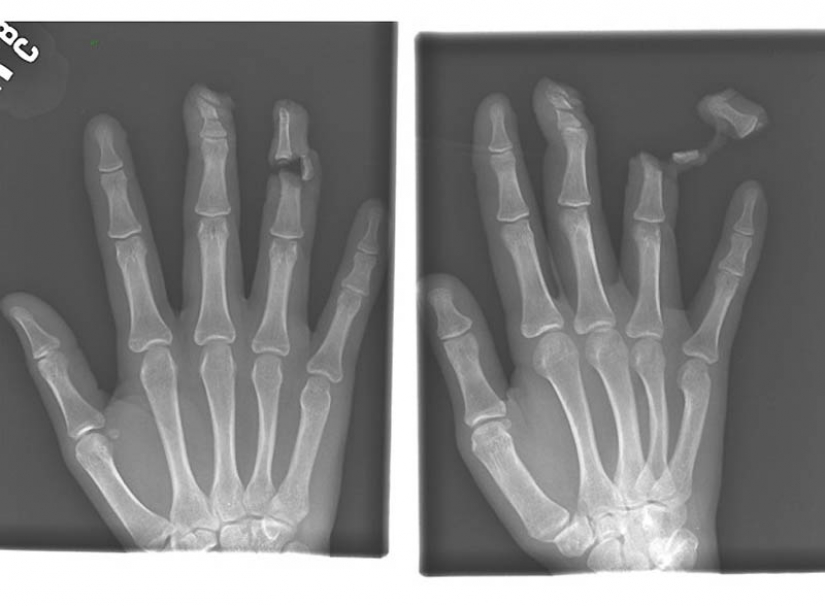

4. The nail in the bones of the index and middle fingers of adult men.

9. Severed finger of a patient who had a fight with a man armed with a knife.